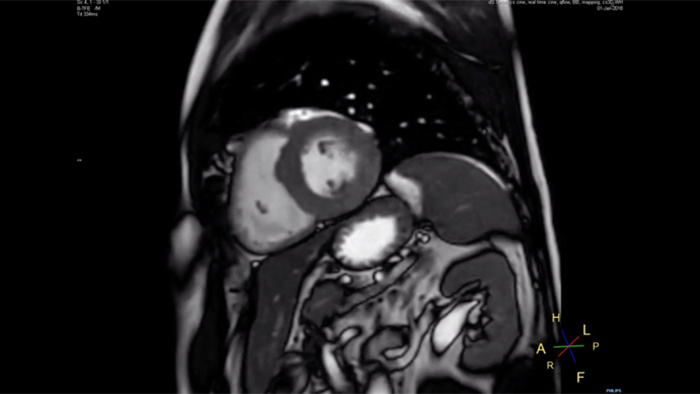

Short breath holds, enhanced image quality and scan time

Compare the breath hold time of an MRI scan performed with Compressed SENSE MRI software versus a conventional scanning technique

12 sec breath hold